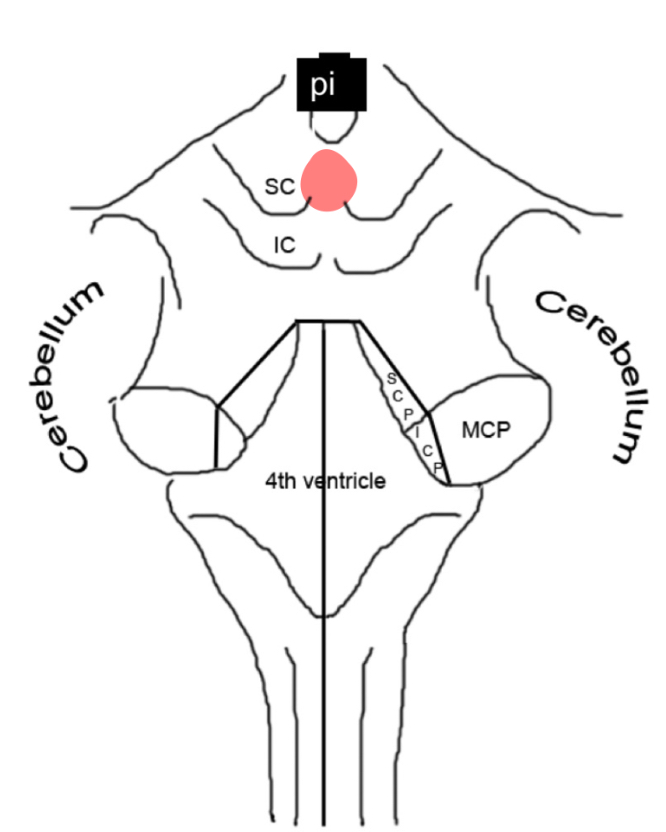

pontine nuclei caudal pons

corticospinal fibers caudal pons

middle cerebellar peduncle caudal pons

pontocerebellar fibers middle pons

corticospinal fibers middle pons

trigeminal nerve middle pons

corticospinal + corticobulbar tracts rostral pons

inferior colliculus caudal midbrain

fastigial nucleus

interposed nucleus (globose + emboliform)

dentate nucleus

cerebellar peduncles

4th ventricle